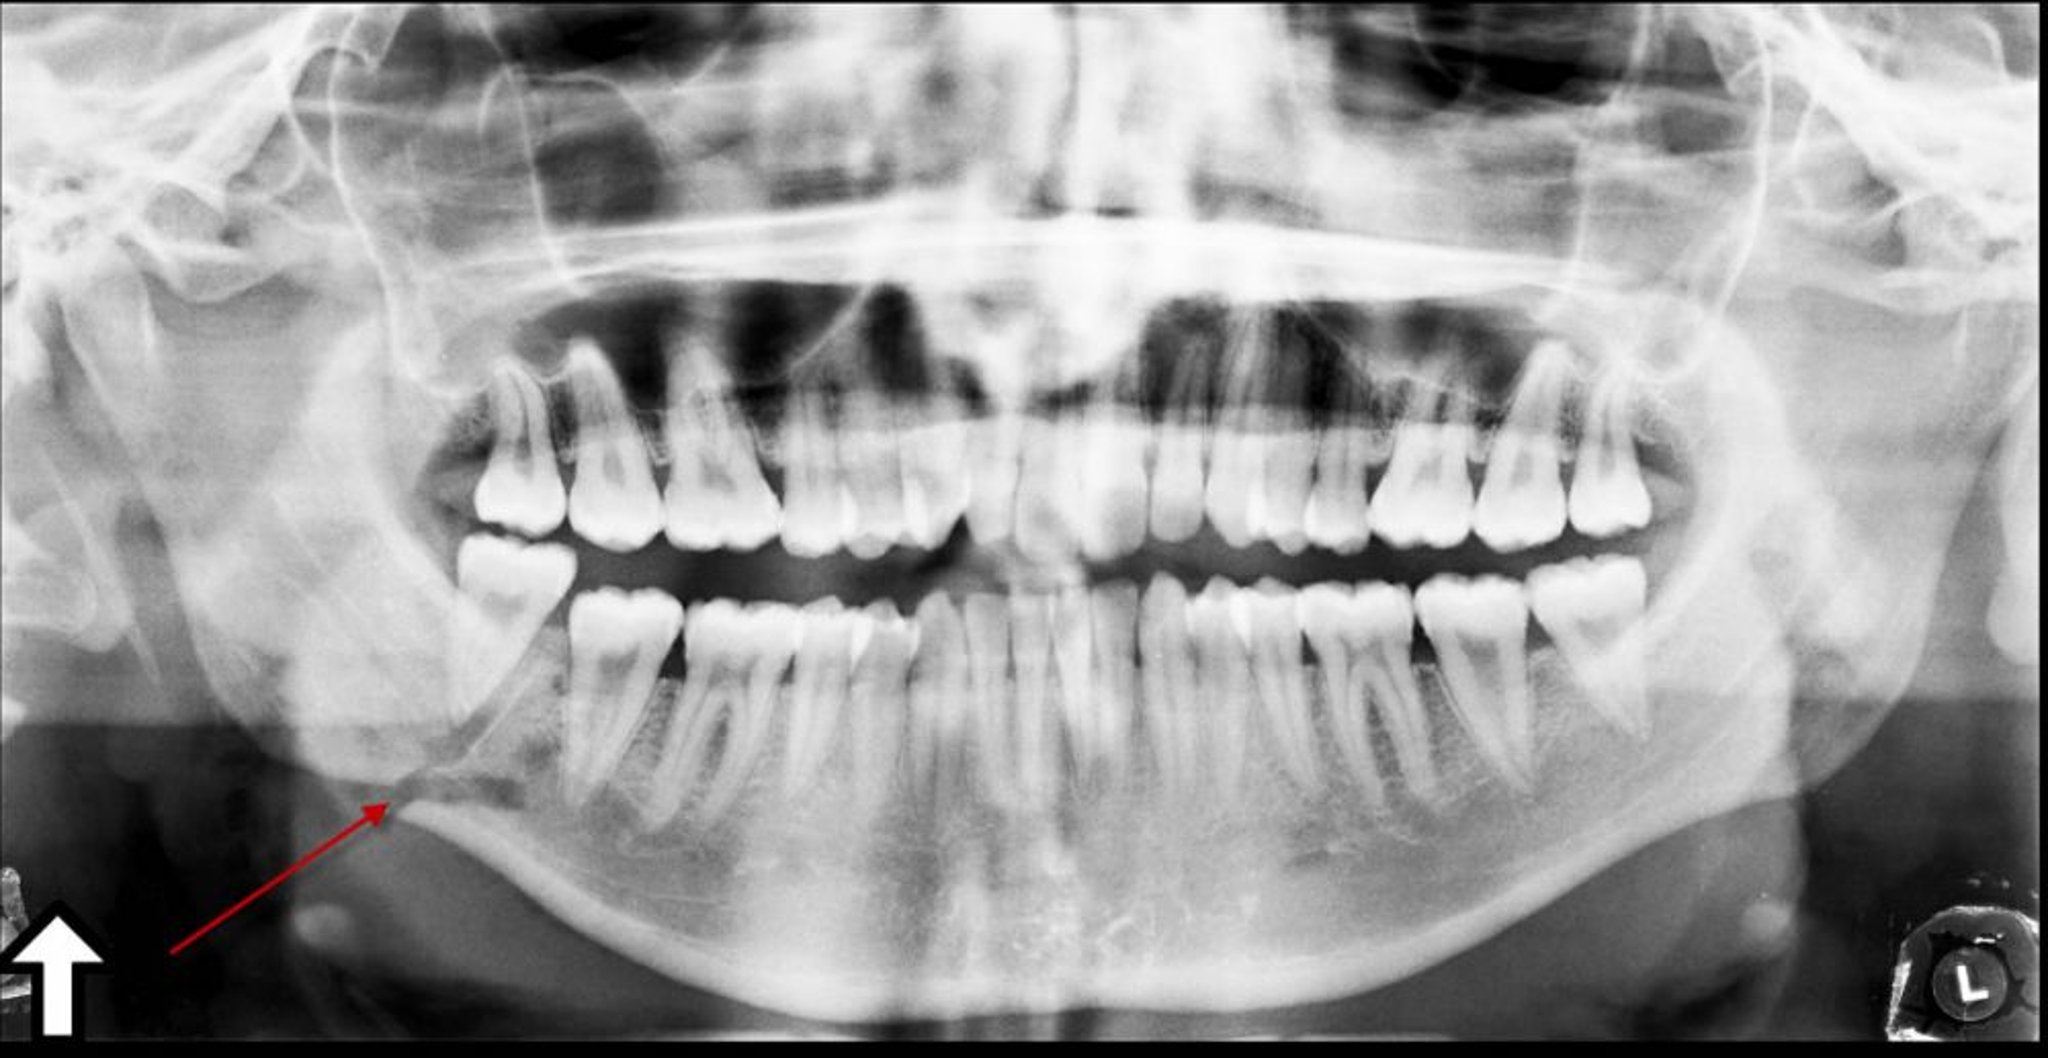

Перелом кута нижньої щелепи

На цій панорамній рентгенограмі видно просвітлення (стрілка) під кутом нижньої щелепи, яке відповідає перелому.